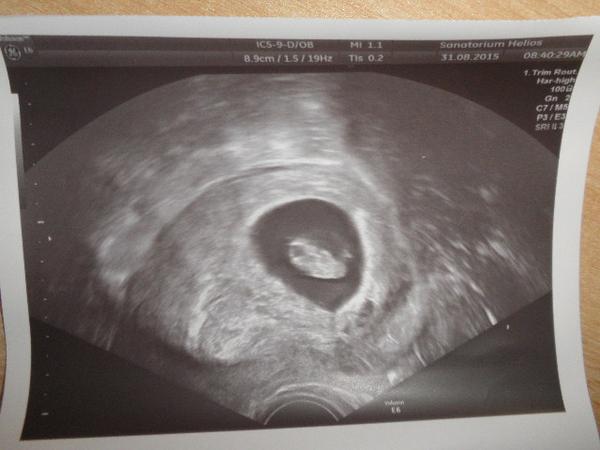

@dadakin to je ale krásná fotečka